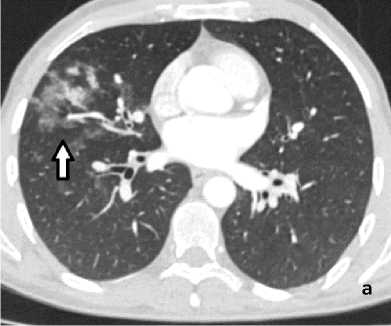

Рисунок 4. КТ грудной клетки с болюсным КУ (артериальная фаза), аксиальные срезы: а (лёгочный режим) – геморрагическое пропитывание в средней доле правого лёгкого (стрелка); б (средостенный режим) – расширение и извитость бронхиальных артерий (сосудистая мальформация – стрелка)

Figure 4. Chest CT with bolus contrast enhancement (arterial phase), axial slices: a (lung window) – hemorrhagic infiltration in the middle lobe of the right lung (arrow); б (mediastinal window) – dilation and tortuosity of bronchial arteries (vascular malformation – arrow)

При КТ-исследовании косвенным признаком состоявшегося ЛК является геморрагическое пропитывание лёгочной ткани в виде зоны неоднородного повышения плотности от «матового стекла» до мягкотканных значений с визуализаций просвета бронхов (рис. 4, а). Локализация пропитывания в большинстве случаев позволяет установить бассейн повреждённого сосуда. КТ-признаком продолжающего кровотечения является эктравазация контрастного препарата в виде гиперденсивных участков неправильной формы, появляющихся в артериальную фазу (при артериальном кровотечении) и увеличивающихся по размеру в последующие фазы КУ. КТ позволяет выявить не только признаки кровоизлияния, но и в большинстве случаев причину его возникновения (рис. 4, б).